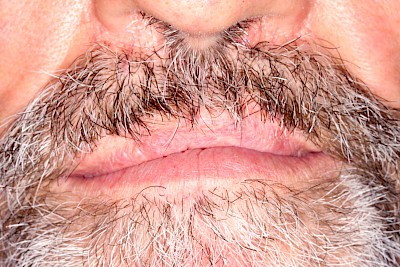

Abzugshilfen

Das Herausnehmen von Zahnprothesen ist mitunter schwierig. Grundsätzlich können leichte Rüttelbewegungen das Herausnehmen erleichtern. Die Prothese sollten immer gut – am besten auf beiden Seiten gleichzeitig – mit Daumen und Zeigefinger gehalten werden, damit die Prothese nicht unbeabsichtigt aus den Fingern nach hinten in den Rachen fällt. Bei Klammerprothesen sollte direkt an den Klammern von unten angesetzt und gleichzeitig von oben gegengehalten werden. Bei Riegelprothesen müssen zunächst die Riegel (in der Regel gibt es zwei Riegel – einen auf der linken und einen auf der rechten Seite) geöffnet werden. Wenn sich die Prothese festhakt, ist es am besten, die Prothese einfach wieder zurückzudrücken und erneut einen Versuch zu starten.

Manchmal werden an den Prothesen auch spezielle Abzugshilfen eingearbeitet. Kompressen als Hilfsmittel können geeignet sein und schließlich gibt es auch im Handel sogenannte Prothesenabzieher.

Klemmt eine Prothese oder bestehen Unsicherheiten beim Herausnehmen, sollte ein Zahnarzt gerufen werden.

Beispiele 21 Bilder